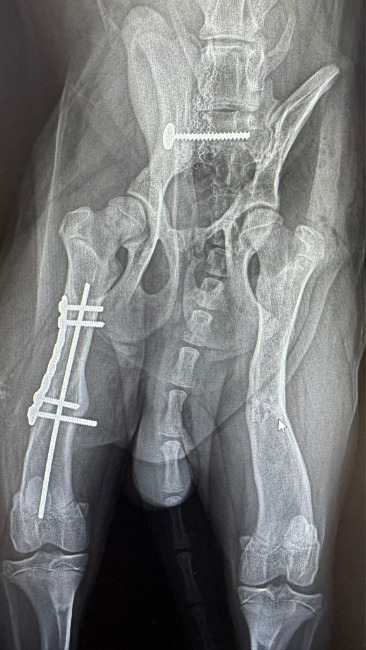

Klimek miał kilka miesięcy kiedy został potrącony przez samochód. Słaby układ kostny szczenięcia nie wytrzymał tak silnego uderzenia, złamaniu uległy obie tylne łapy oraz miednica.

Zespół weterynarzy spędził przy stole operacyjnym wiele godzin, zanim udało im się poskładać Klimka w jedną całość.

Podczas drugiej operacji, która odbyła się 24.02.2026 Klimek "pozbył" się jednej śruby, która mocowała miednicę oraz gwoździa z lewej łapy.

21.04.2026 po raz kolejny musimy zawieźć psiaka do lecznicy, i po raz kolejny położyć go na stole operacyjnym. Tym razem trzeba usunąć drugą śrubę z miednicy, zabieg ten ma na celu poprawienie ruchomości układu kostnego, który rośnie razem z psem, a jest ograniczona właśnie tym implantem.